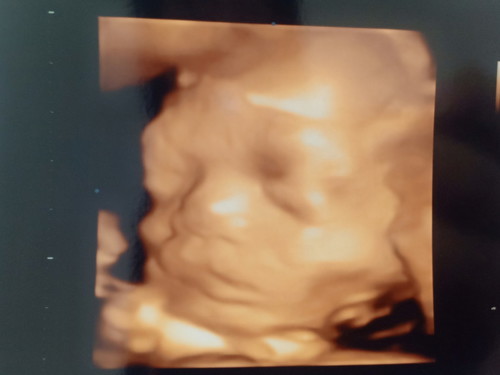

ท้อง7เดือน

รูปซาวด์ตอน28 w 5 d ขอดูรูปแม่ๆคลอดเดือน ม.ค หน่อยค่ะ